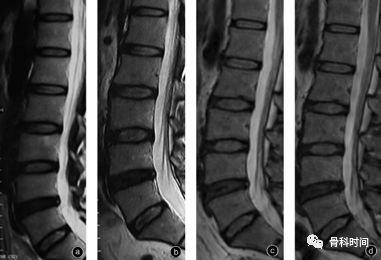

髓核脱水表现,纤维环撕裂表现和软骨终板形成裂隙表现,进一步发展为

椎间盘变性:椎间盘高度的减低及髓核t2wi信号降低,及髓核与纤维环的